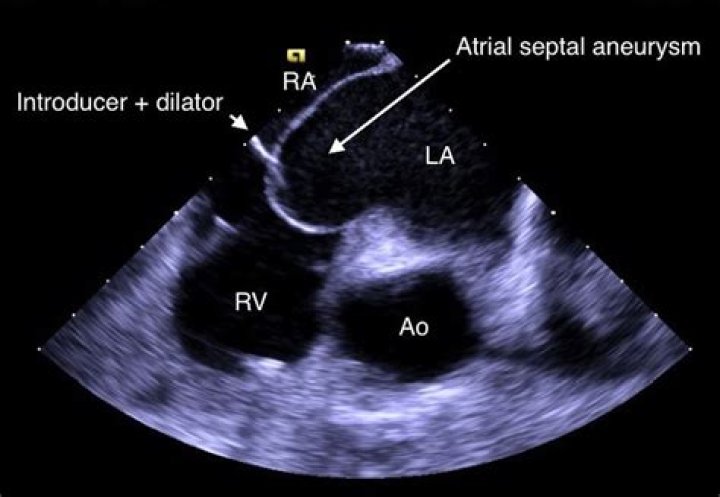

Introduction. Atrial septal aneurysm (ASA) is a congenital deformity of interatrial septum consisting redundant and mobile interatrial septal tissue in the region of fossa ovalis with bulging into the right or left atrium and sometimes oscillating between both atria.

It is a localized bulging of the inter-atrial septum into either or both atria during the cardiac cycle. ASA has been reported as an unexpected finding during autopsy but may also be diagnosed in living patients by echocardiographic techniques...

The interatrial septum is the thin wall that separates the upper atrial cavities of heart. When it appears elongated and “floppy” on cardiac ultrasound, we call it “aneurysmal”. This is a condition that some people are born with. It alone portends no prognostic risk.